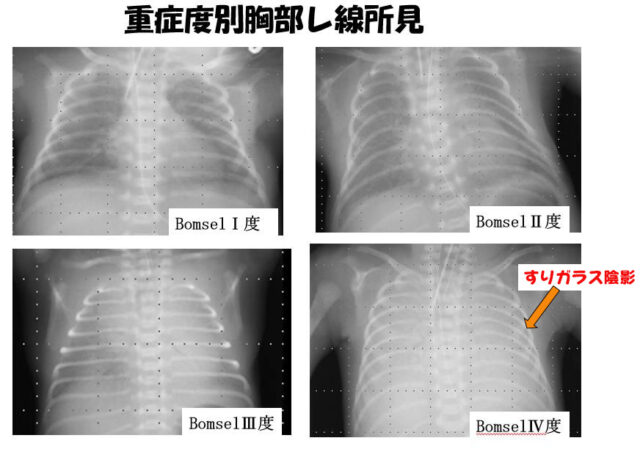

【期間限定!最安値挑戦】 症例に学ぶ新生児X線診断 語学+参考書の詳細情報

症例に学ぶ新生児X線診断。新版胸部単純X線診断: 画像の成り立ちと読影の進め方 | 林 邦昭。目でみる症例 ニューモシスチス肺炎 (臨床雑誌内科 95巻4号。

症例に学ぶ新生児X線診断

症例に学ぶ新生児X線診断